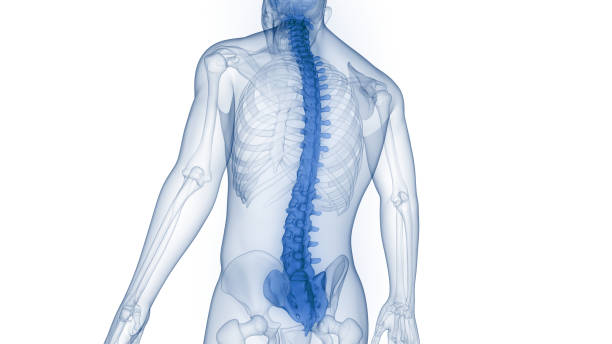

✅척추전방전위란?

척추는 원래 바로 떨어져 있어야 합니다. 하지만 전방 전위는 척추가 앞으로 치우쳐져 있는 상태를 말합니다. 이는 크게 두 가지 원인으로 나눌 수 있습니다.